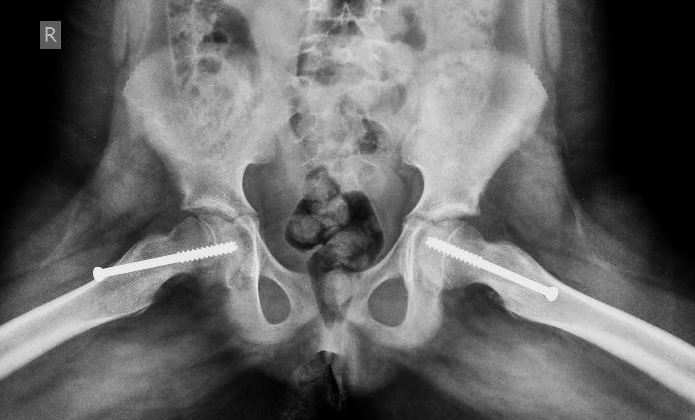

The goal of treatment is to prevent the femoral head from further slippage. This usually needs surgery which may be:

* Fixing a metal screw to prevent the femoral head from slipping further.

There is a considerable risk of the opposite hip also sustaining the same condition in the future; this risk is more if the child is younger than usual age (less than 10 years), child has a hormone related problem or if there is a kidney disease. In these situations the doctor decides to put a screw in the opposite hip also in order to prevent a slip which might happen in the that hip.